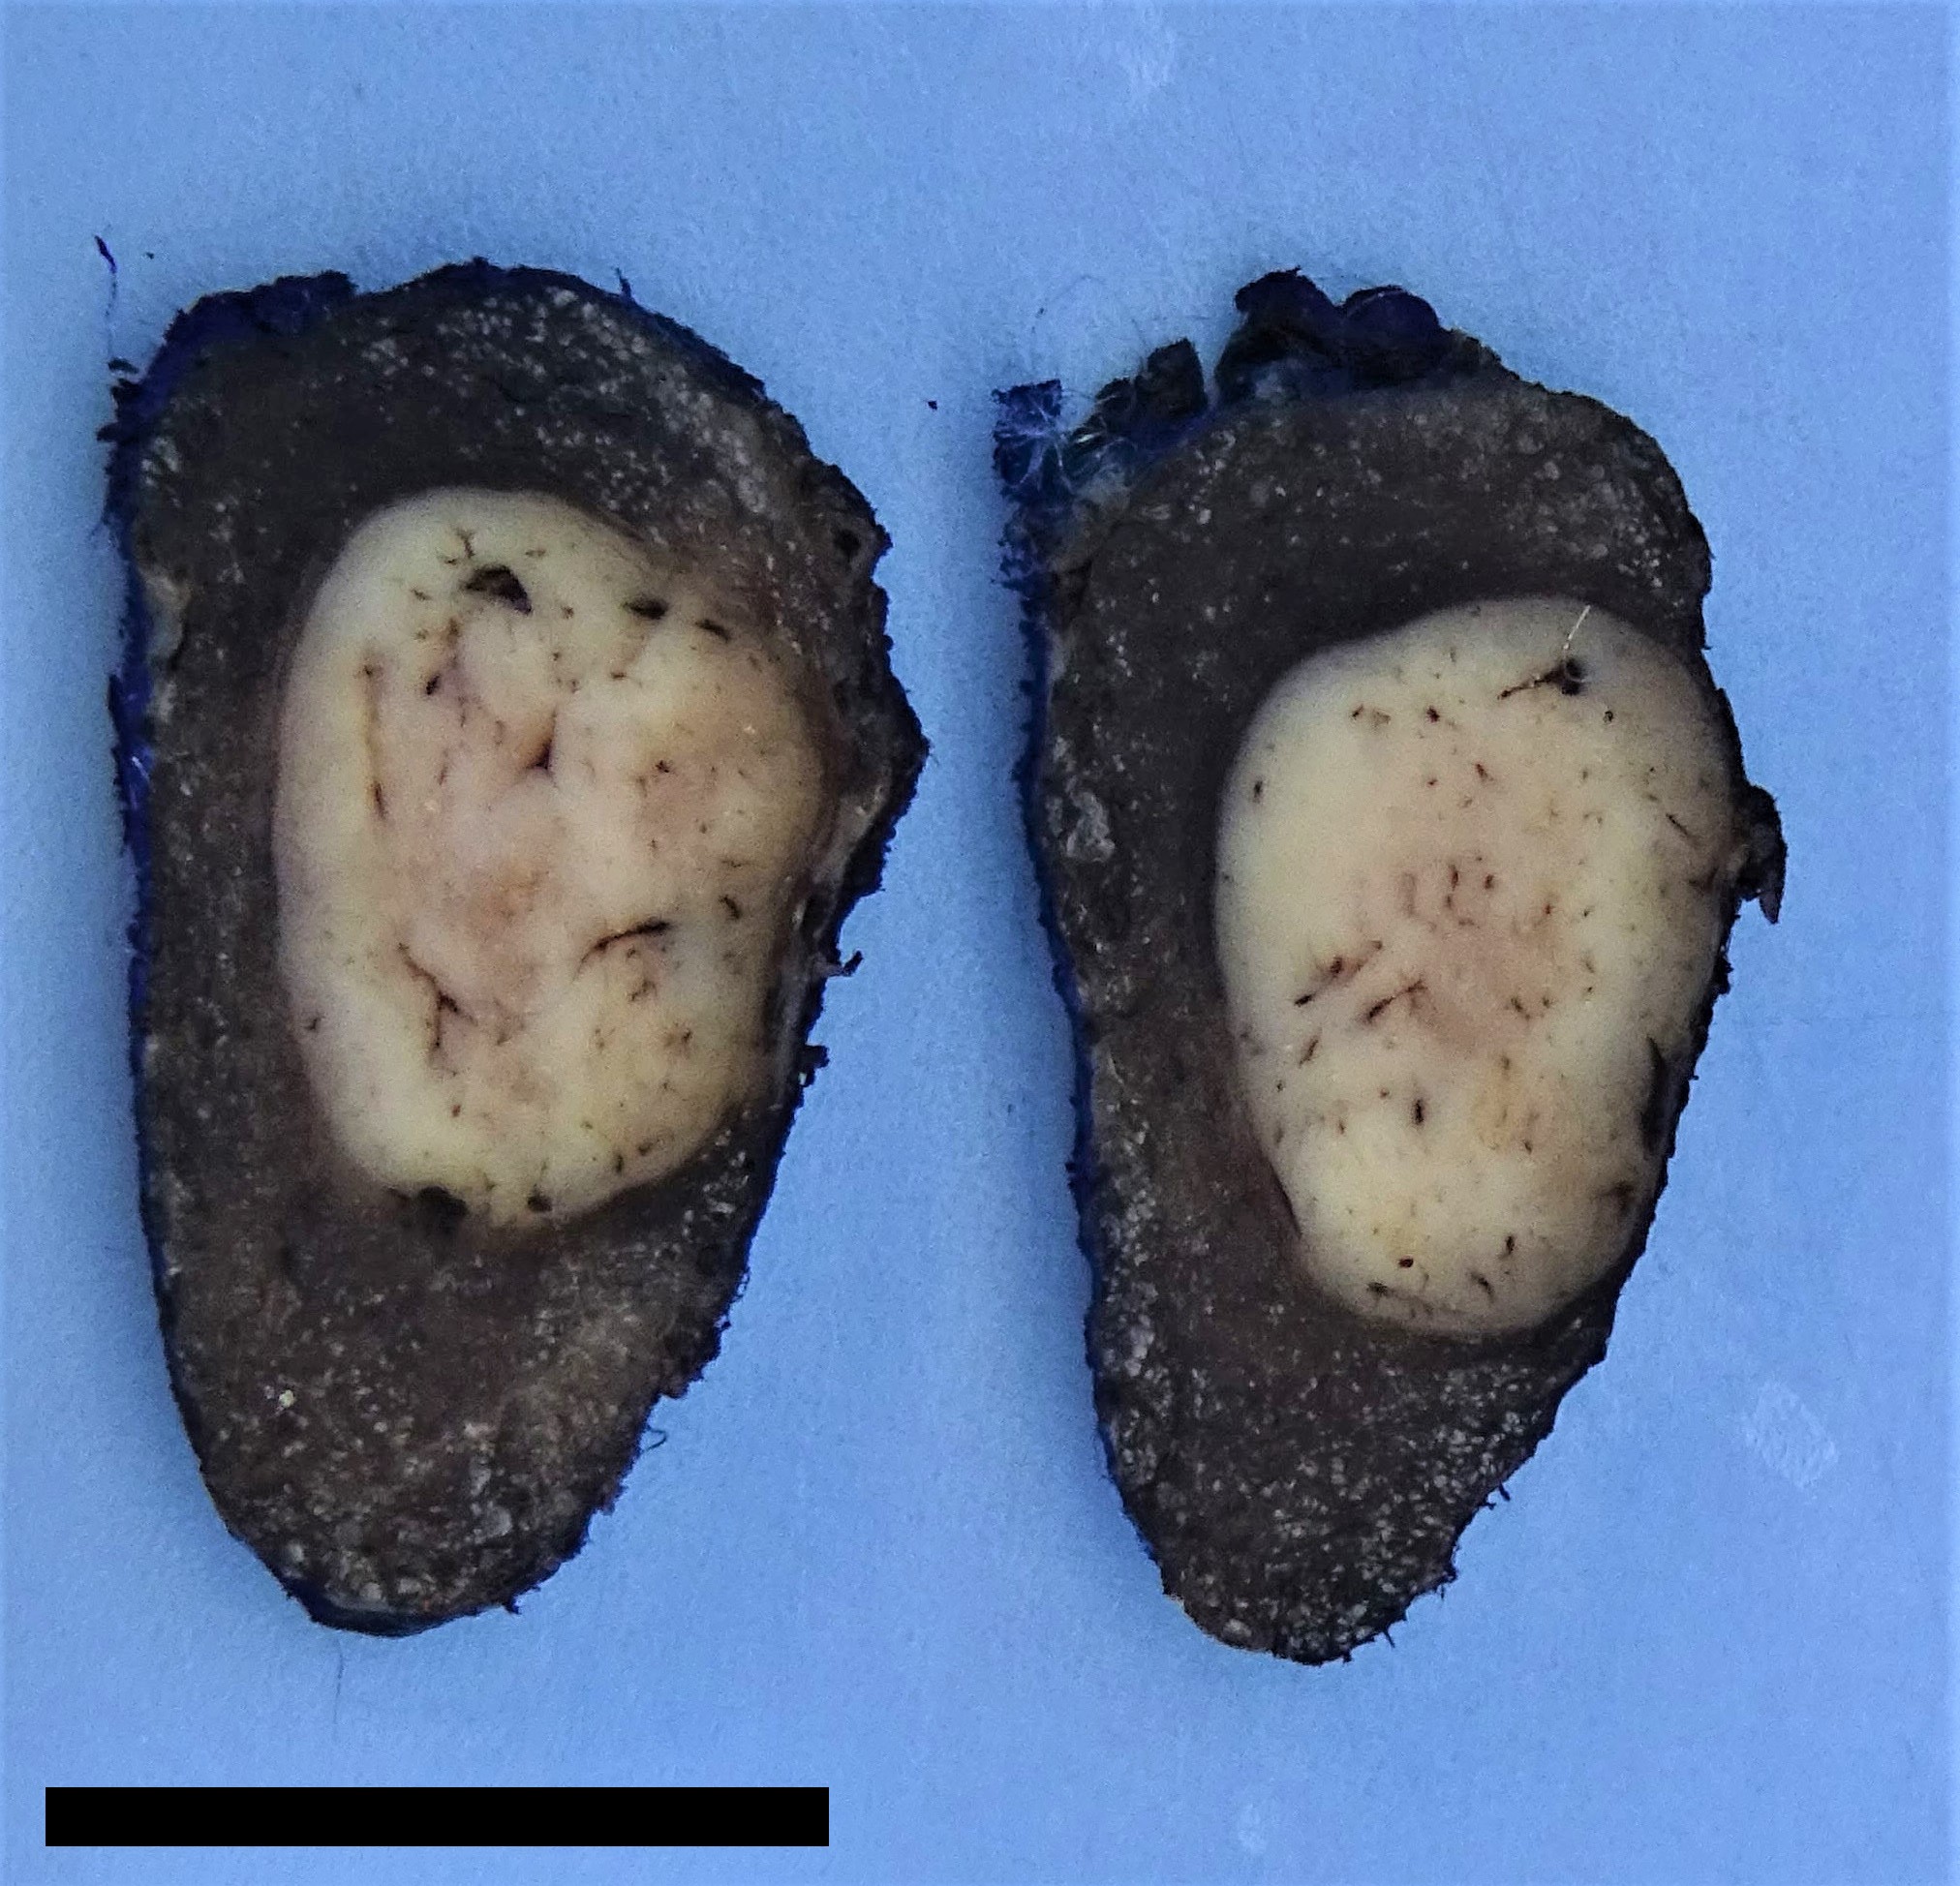

Gross description

- Encapsulated follicular variant: well circumscribed solid beige to tan mass with or without a grossly appreciable tumoral capsule

Gross images